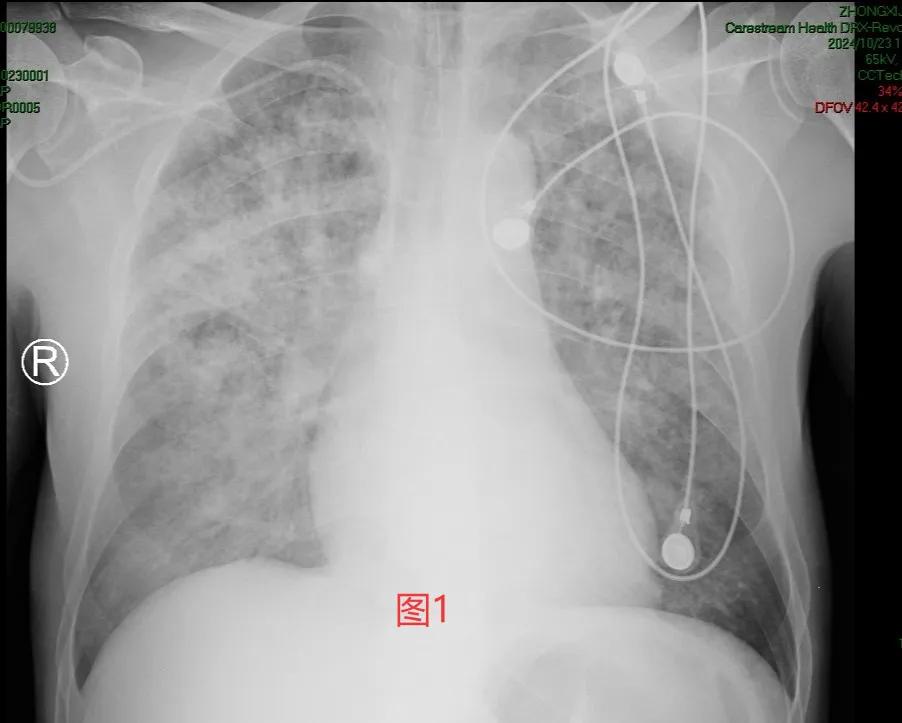

一个念头闪现,难道是“弥漫性肺泡出血综合征”?马上拍了个床边片(图1)。哇!还真有可能是它。

弥漫性肺泡出血综合征(diffuse alveolar hemorrhage syndrome,DAHS)是以痰中带血、咯血、呼吸困难、进行性贫血和胸部X线或CT影像呈弥漫性肺泡浸润为特征的临床综合征[1]。DAHS临床较为少见,多数起病急骤,病因复杂,如感染、中毒、药物、化学物质、细胞毒药物、自身免疫系统性疾病、系统性血管炎、血液系统疾病、造血干细胞移植等均可导致DAHS。